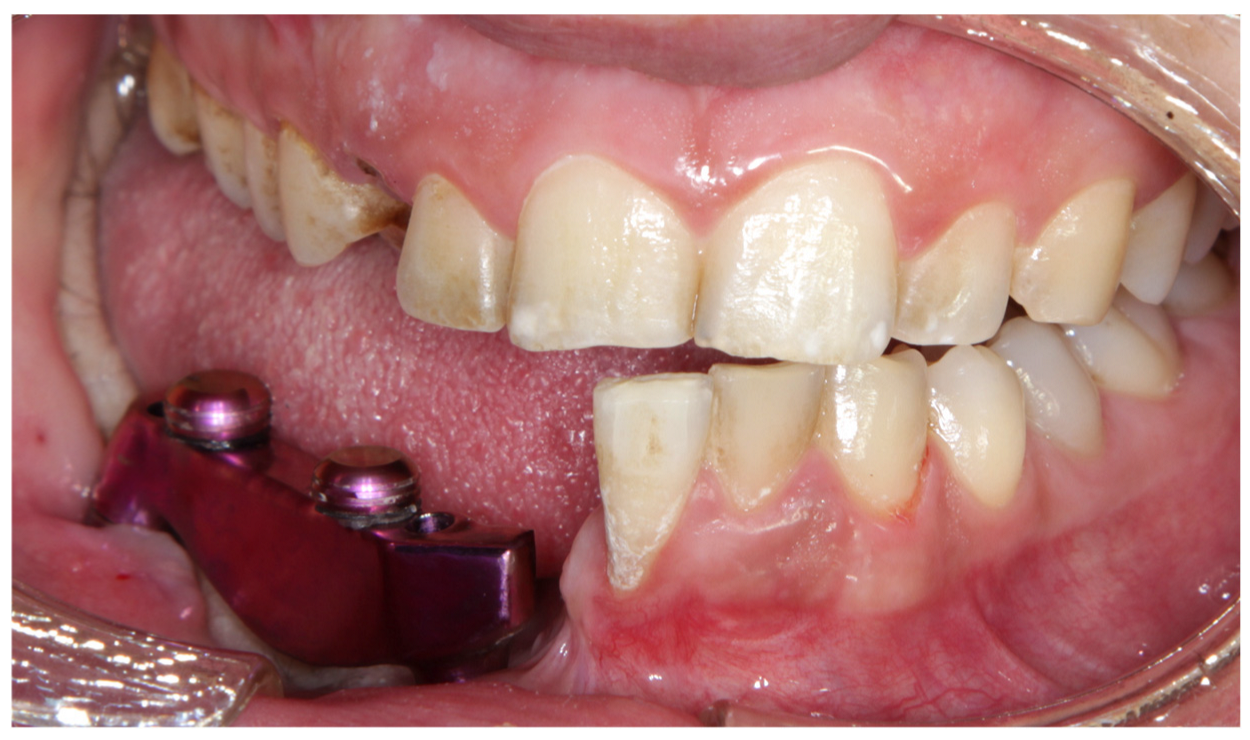

| 2023 | Surgery of 4 implants in the jaw |

| 2023 | Removal of 2 dental implants |

| 2023–2024 | Start with rehabilitation phase |